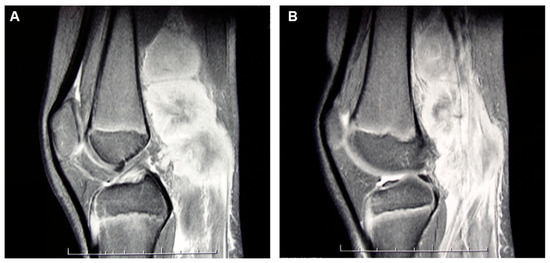

3. Case Presentation